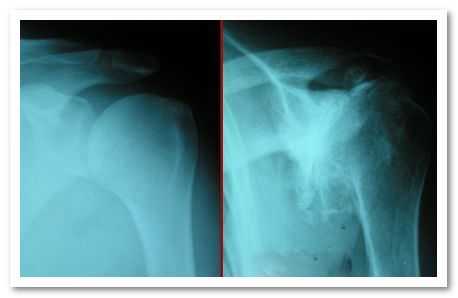

Также на второй стадии артроза на рентгеновском снимке отмечаются симптомы: сужение суставной щели, появление остеофитов (костных наростов) и утолщение суставных поверхностей костей. Можно заметить и некоторую атрофию мышц в области плеча.

На фото – рентген-снимок. Слева – норма, справа – очень маленькая суставная щель в плече

При этом на рентгеновских снимках наблюдается так называемый «симптом кольца», когда изображение суставной впадины принимает вид овального кольца.

На снимках отмечается сужение суставной щели, утолщение суставных поверхностей, а также появление остеофитов.